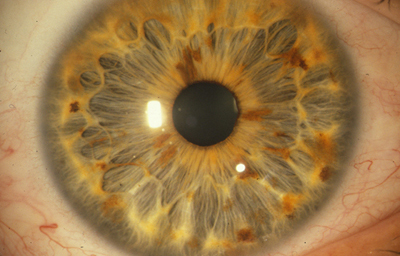

El Iris se divide 2 regiones principales:

1- La Zona Pupilar es la región mas interna que conforma el borde de la pupila ;(desde el borde periférico del collarete)

2- La Zona Ciliar es el resto del iris y se extiende hasta su origen en el cuerpo ciliar

El Collarete que separa la zona pupilar de la ciliar y es la porción mas gruesa del iris, es un vestigio de la cubierta de la pupila embrionaria. La Raiz de iris es la porción mas periférica y la mas delgada, esta unida a la esclera y a la porción anterior del Cuerpo Ciliar. El Iris y el Cuerpo Ciliar componen la Úvea Anterior.

En la cara Anterior esta el pigmento que le da el color al Iris y dependiendo del grado de reabsorción u atrofia de esa capa anterior se pueden observar:

Las Criptas de Fuchs: que son pequeñas aberturas alrededor del collarete, producto de la atrofia o reabsorción de la hoja anterior del iris, que le permiten al estroma y a los tejidos mas profundos estar en contacto con el humor acuoso.

El Color del Iris

El Iris en general es muy pigmentado con colores que comúnmente van del marrón, avellana, gris, verde y azul. Existen los iris sin pigmento en el Albinismo oculo-cutáneo en cuyo caso se ven blanco/rosados.

El color del Iris es un fenómeno complejo por efectos combinados por la textura, la pigmentación y el tejido fibrovascular del estroma, junto con la constitución epigenética del individuo. Desde el punto de vista óptico, la simple absorción o reflexión selectiva por algunas moléculas, como la hemoglobina o el colágeno del estroma que son componentes no pigmentados, puede tener influencia en el color que es observado.

A pesar de la gran variedad en el color del Iris, el único pigmento que contribuye en forma sustancial es la melanina; su cantidad, es uno de los factores que determina el color del iris en una persona. Estructuralmente el color depende de la cantidad variable de eumelanina (melaninas marron/negra) y pheomelanina (melaninas rojo/amarillo) producidas por los melanocitos derivados de la Cresta Neural. El grado de dispersión de la melanina que yace en racimos subcelulares en los melanosomas, tiene cierta influencia en el color que se observa, pero el grado de dispersión no es reversible ya que los melanosomas no son moviles.

La Heterocromia Iridis y la Heterocromia Parcial o Sectorial

Son variantes, en la que un Iris es completamente diferente en color al Iris del otro ojo, o un Iris tiene un sector de diferente color a otro sector; es poco común y frecuentemente se asocia con enfermedades oculares, pero existen en los humanos como variantes normales.